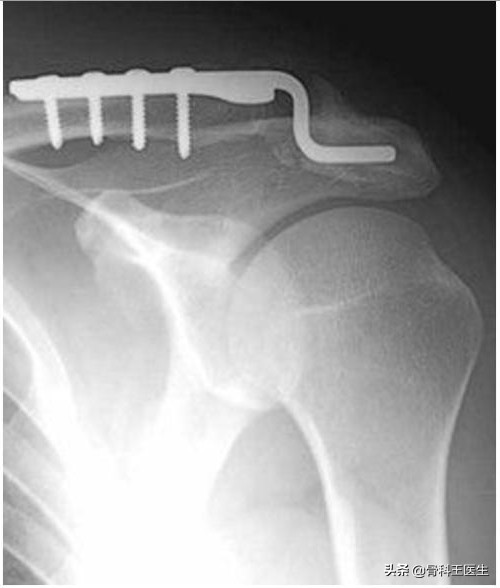

1、用钢板把锁骨压下去: